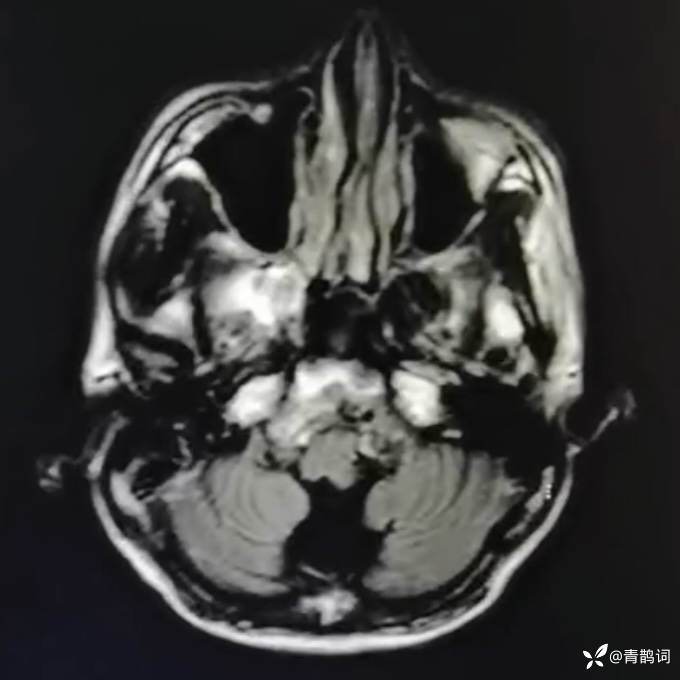

乐痴于医等 2人推荐简要病史:42岁男性,记忆力下降及听力下降一年余。既往体健,否认前驱感染病史。否认家族史。三个月前就诊于当地医院,自述腰穿脑脊液乳酸增高。现就诊于我院,查体记忆力下降,计算力下降,定时定向差,吟诗样语言。完善磁共振如下:

2.患者小脑萎缩严重,和大脑半球的病灶之间有无关系?能否用一元论解释?